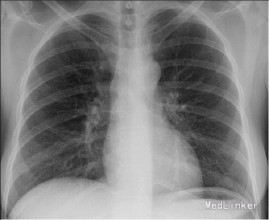

患者,女性,19岁,咳嗽,发热,左侧胸痛15天,加重伴呼吸困难5天入院。该患者于15天前无明显诱因出现咳嗽,干咳为主,伴发热,体温波动在37.5-38.0°,以午后为主,左侧胸痛明显,同呼吸运动有关,每当深吸气时加剧,在当地医院静脉滴注头孢类抗生素治疗10天后咳嗽发热症状未见明显缓解,5天前胸痛症状消失,但出现明显的呼吸困难,为明确诊断收治入院。病程中伴有盗汗、周身乏力、食欲减退。 患者既往无其他系统性疾病,其父有肺结核病史。

体温37.9°,气管右侧移位,左侧胸廓饱满,触觉语颤减弱,叩诊呈浊音,听诊呼吸音消失。其四肢大关节附近可见结节性红斑,间歇出现。 胸片:左肺胸腔积液 PPD试验:强阳性 痰涂片结果:发现结核杆菌 胸腔积液结果:淋巴细胞为主,间皮细胞<5%,蛋白质多>40g/L,腺苷脱氧酶(ADA)增高,沉渣找到结核杆菌。

诊断:结核性胸膜炎 治疗:1、胸腔穿刺把积液抽出 2、早起、规律、全程、足量、联合使用抗痨药物